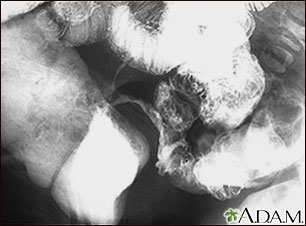

Esta radiografía del abdomen inferior muestra un estrechamiento (estenosis) del extremo distal del intestino delgado (ileon), resultado de la enfermedad de Crohn. Esta enfermedad típicamente afecta el intestino delgado, mientras que la colitis ulcerativa afecta el intestino grueso. Esta radiografía fue tomada después de dar a beber al paciente una solución con un medio de contraste (bario), al momento en que ésta pasó por el intestino delgado (serie GI inferior).